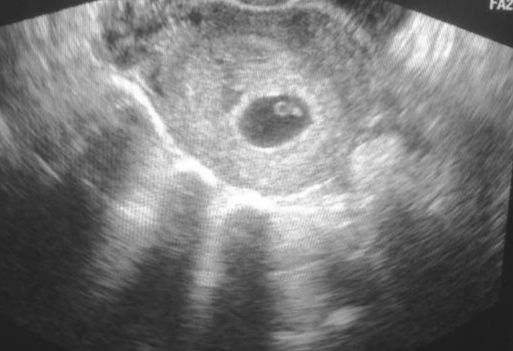

Сегодня 33 дпо, по месячным 6.6 недель, по моим подсчетам 6.3, т. к. цикл 26 и О позже на 2 дня. На узи всё развивается, нашли ПЯ 8 мм, желточный мешок, ктр 1,5 мм.